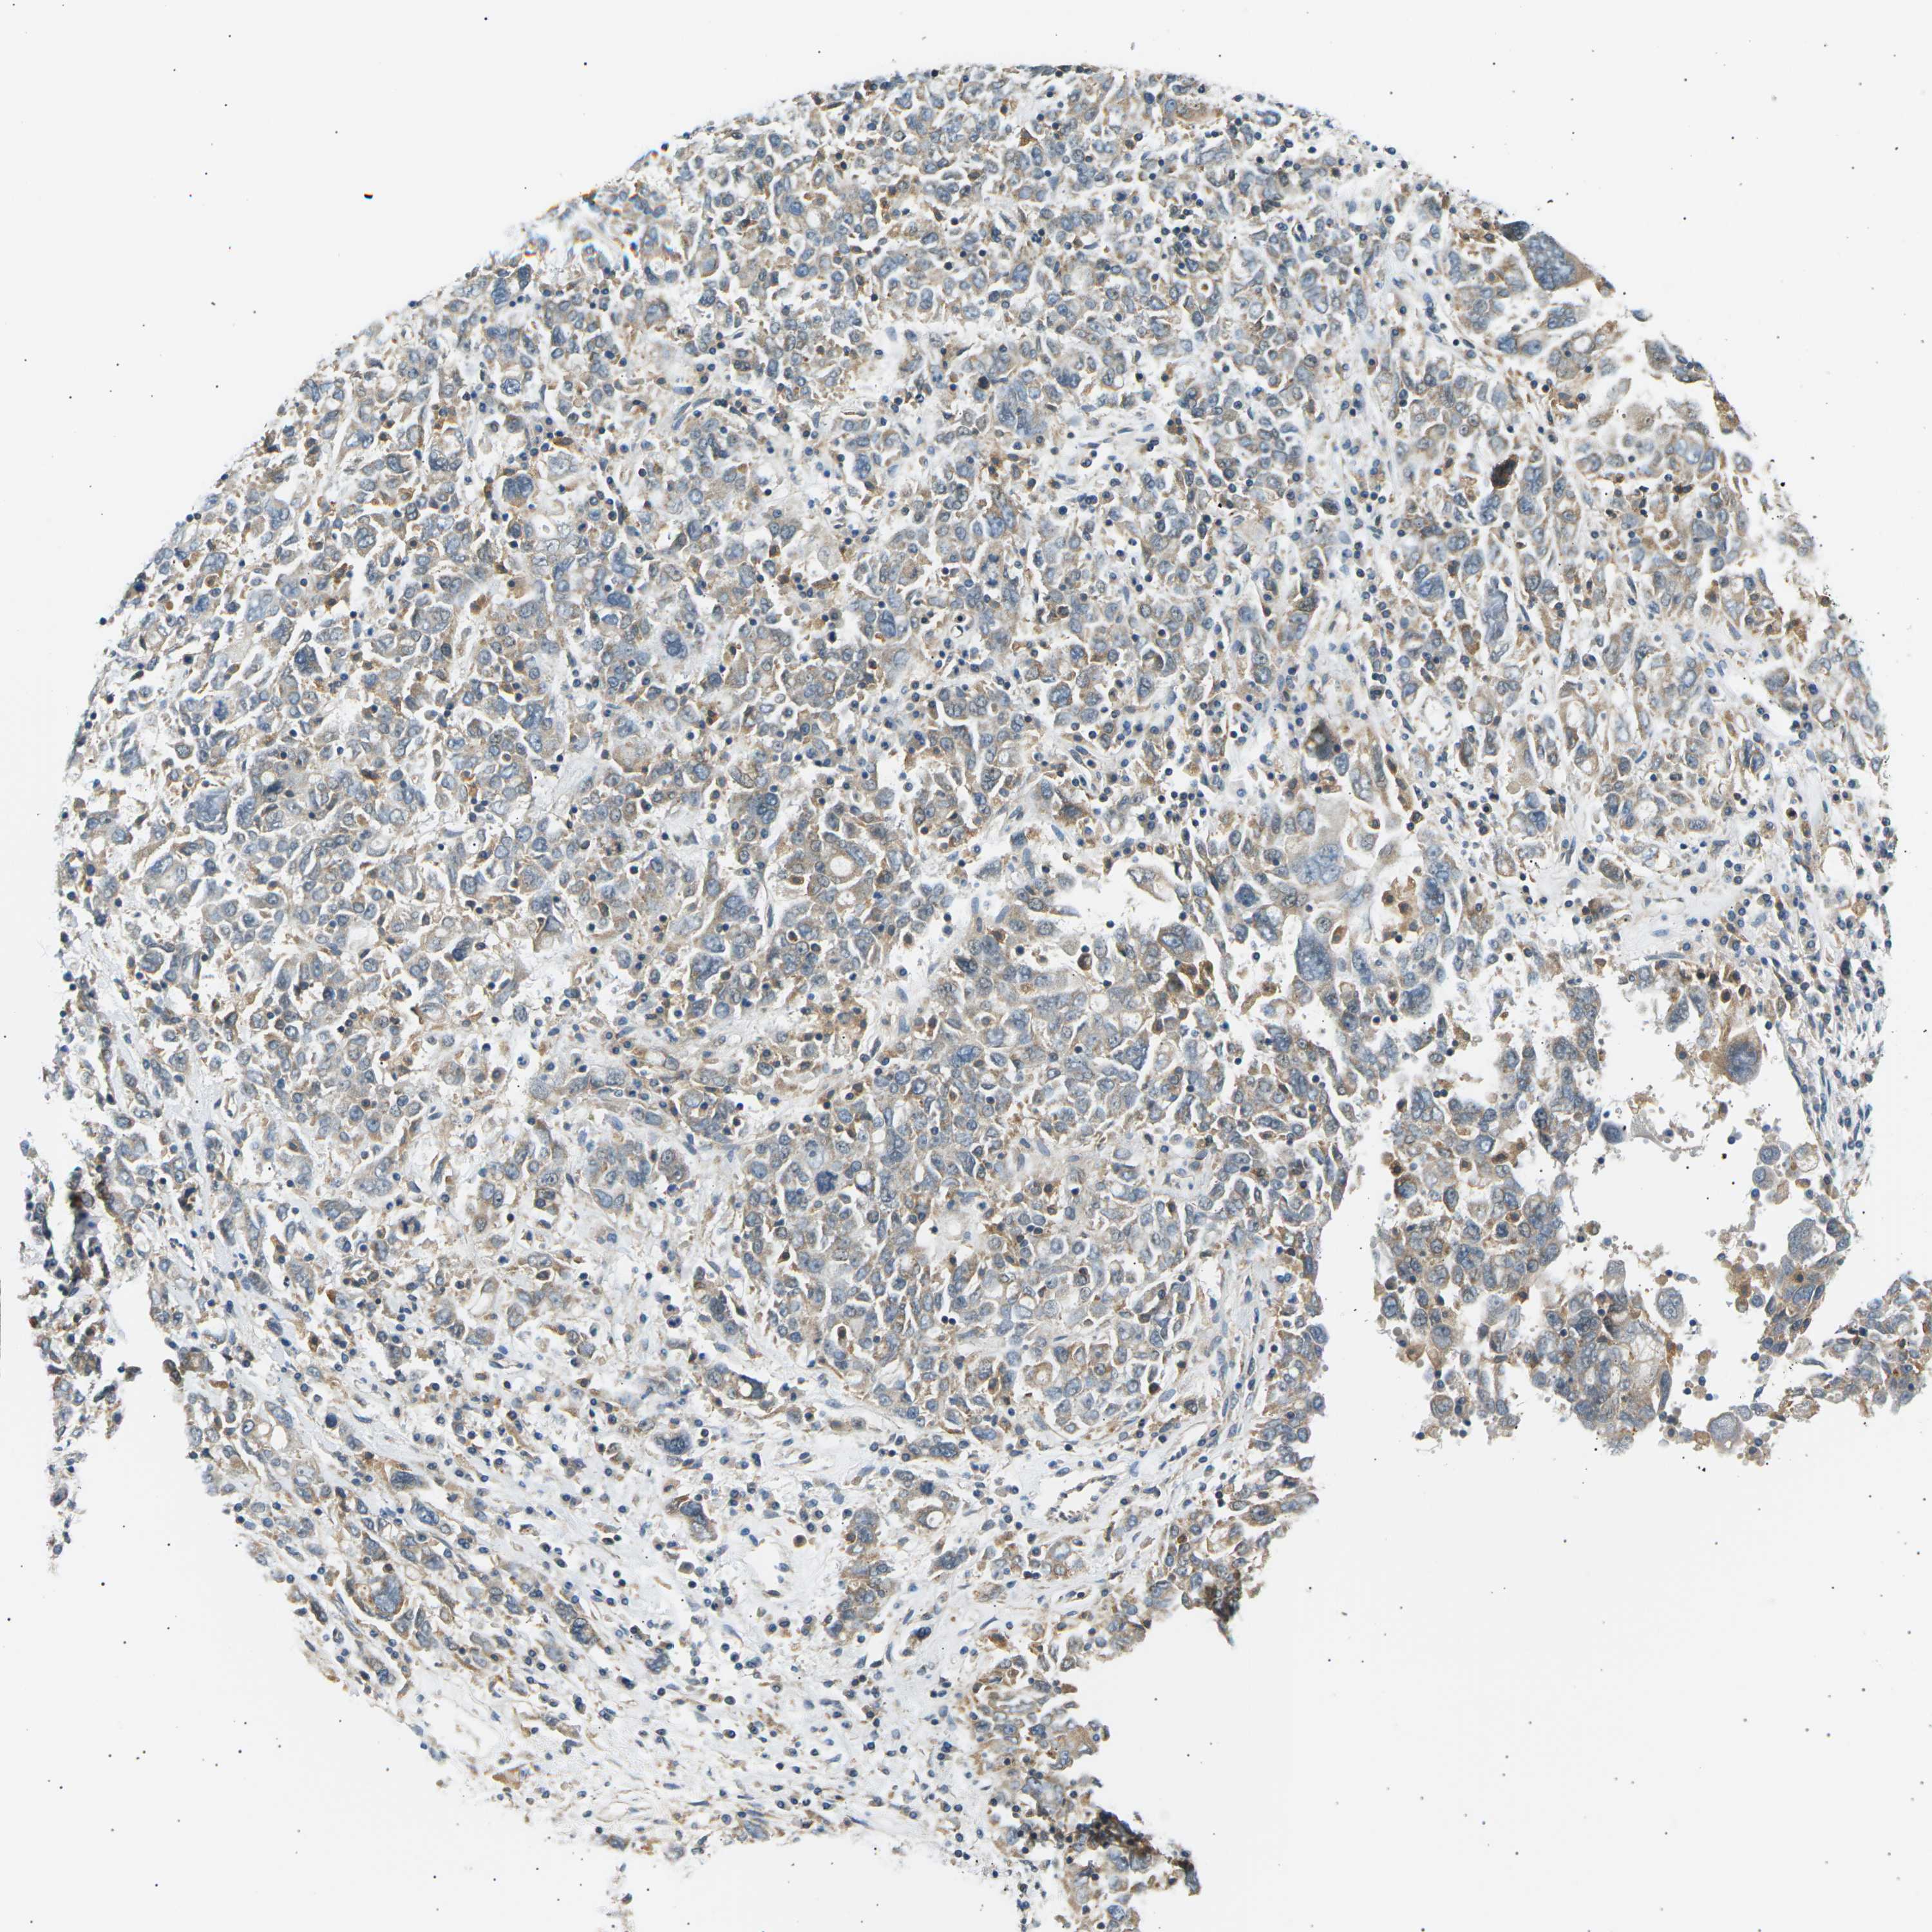

OVARIAN CANCER - Protein expressioni

A mouse-over function shows sample information and annotation data. Click on an image to view it in a full screen mode. Samples can be filtered based on level of antibody staining by selecting one or several of the following categories: high, medium, low and not detected. The assay and annotation is described here.

Note that samples used for immunohistochemistry by the Human Protein Atlas do not correspond to samples in the TCGA dataset.

Antibody stainingi

Antibody staining in the annotated cell types in the current human tissue is reported as not detected, low, medium, or high, based on conventional immunohistochemistry profiling in selected tissues. This score is based on the combination of the staining intensity and fraction of stained cells.

Each image is clickable and will lead to virtual microscopy that enables deeper exploration of all samples and also displays staining intensity scores, fraction scores and subcellular localization as well as patient and tissue information for each sample.

Antibody CAB015211

Staining

High

Medium

Low

Not detected

Intensity

Strong

Moderate

Weak

Negative

Quantity

>75%

75%-25%

<25%

None

Location

Nuclear

Cytoplasmic/membranous

Cytoplasmic/membranous,nuclear

Cystadenocarcinoma, serous, NOS

Carcinoma, endometroid

Cystadenocarcinoma, mucinous, NOS

Carcinoma, NOS